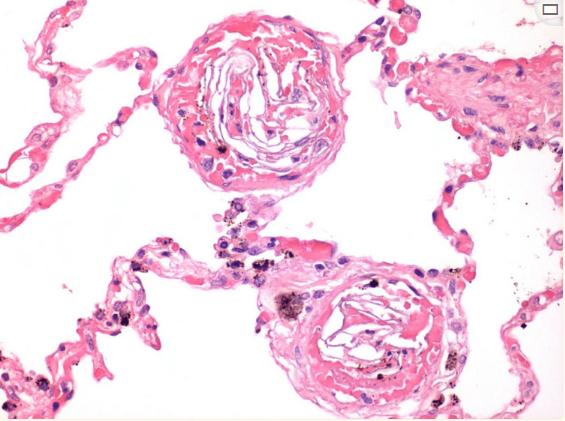

根据母亲的尸检,多器官组织病理学检查结果显示出血和炎症浸润、水肿、无定形嗜酸性物质以及中小血管中的纤维蛋白沉积,提示DIC(图1)。肺血管中出现粘液、胎儿上皮鳞片和胎粪提示ASP诊断(图2)。还存在含铁血黄素颗粒。子宫颈出现多个印痕,这证实了多处脐带缠绕。

图2、病例1肺小血管腔内的纤维蛋白血栓(放大100倍)